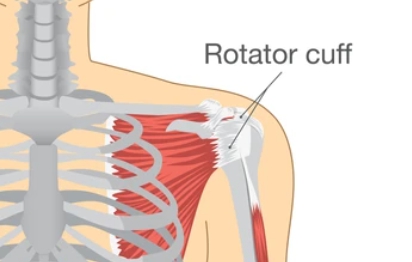

어깨는 주변을 감싸고 있는 ‘회전근개’라는 조직이 있습니다. 이 조직들이 제대로 된 역할을 하지 못하고 찢어지거나 너덜너덜해지고 없어진다면, 어깨 인공관절 치환술을 시행합니다.

(*Rotator cuff가 회전근개입니다. 일반적으로 회전근개가 파열된다면 수술을 통해 회전근개를 보강해 줍니다.)